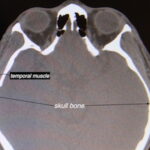

Background:Â Reduction of the wide or convex head shape is most effectively done through muscle removal. The temporal muscle is quite large with its origins along the long temporal line of the skull from which it extends down into a funnel shape through which is passes under the zygomatic arch. Once under the arch this Read More…